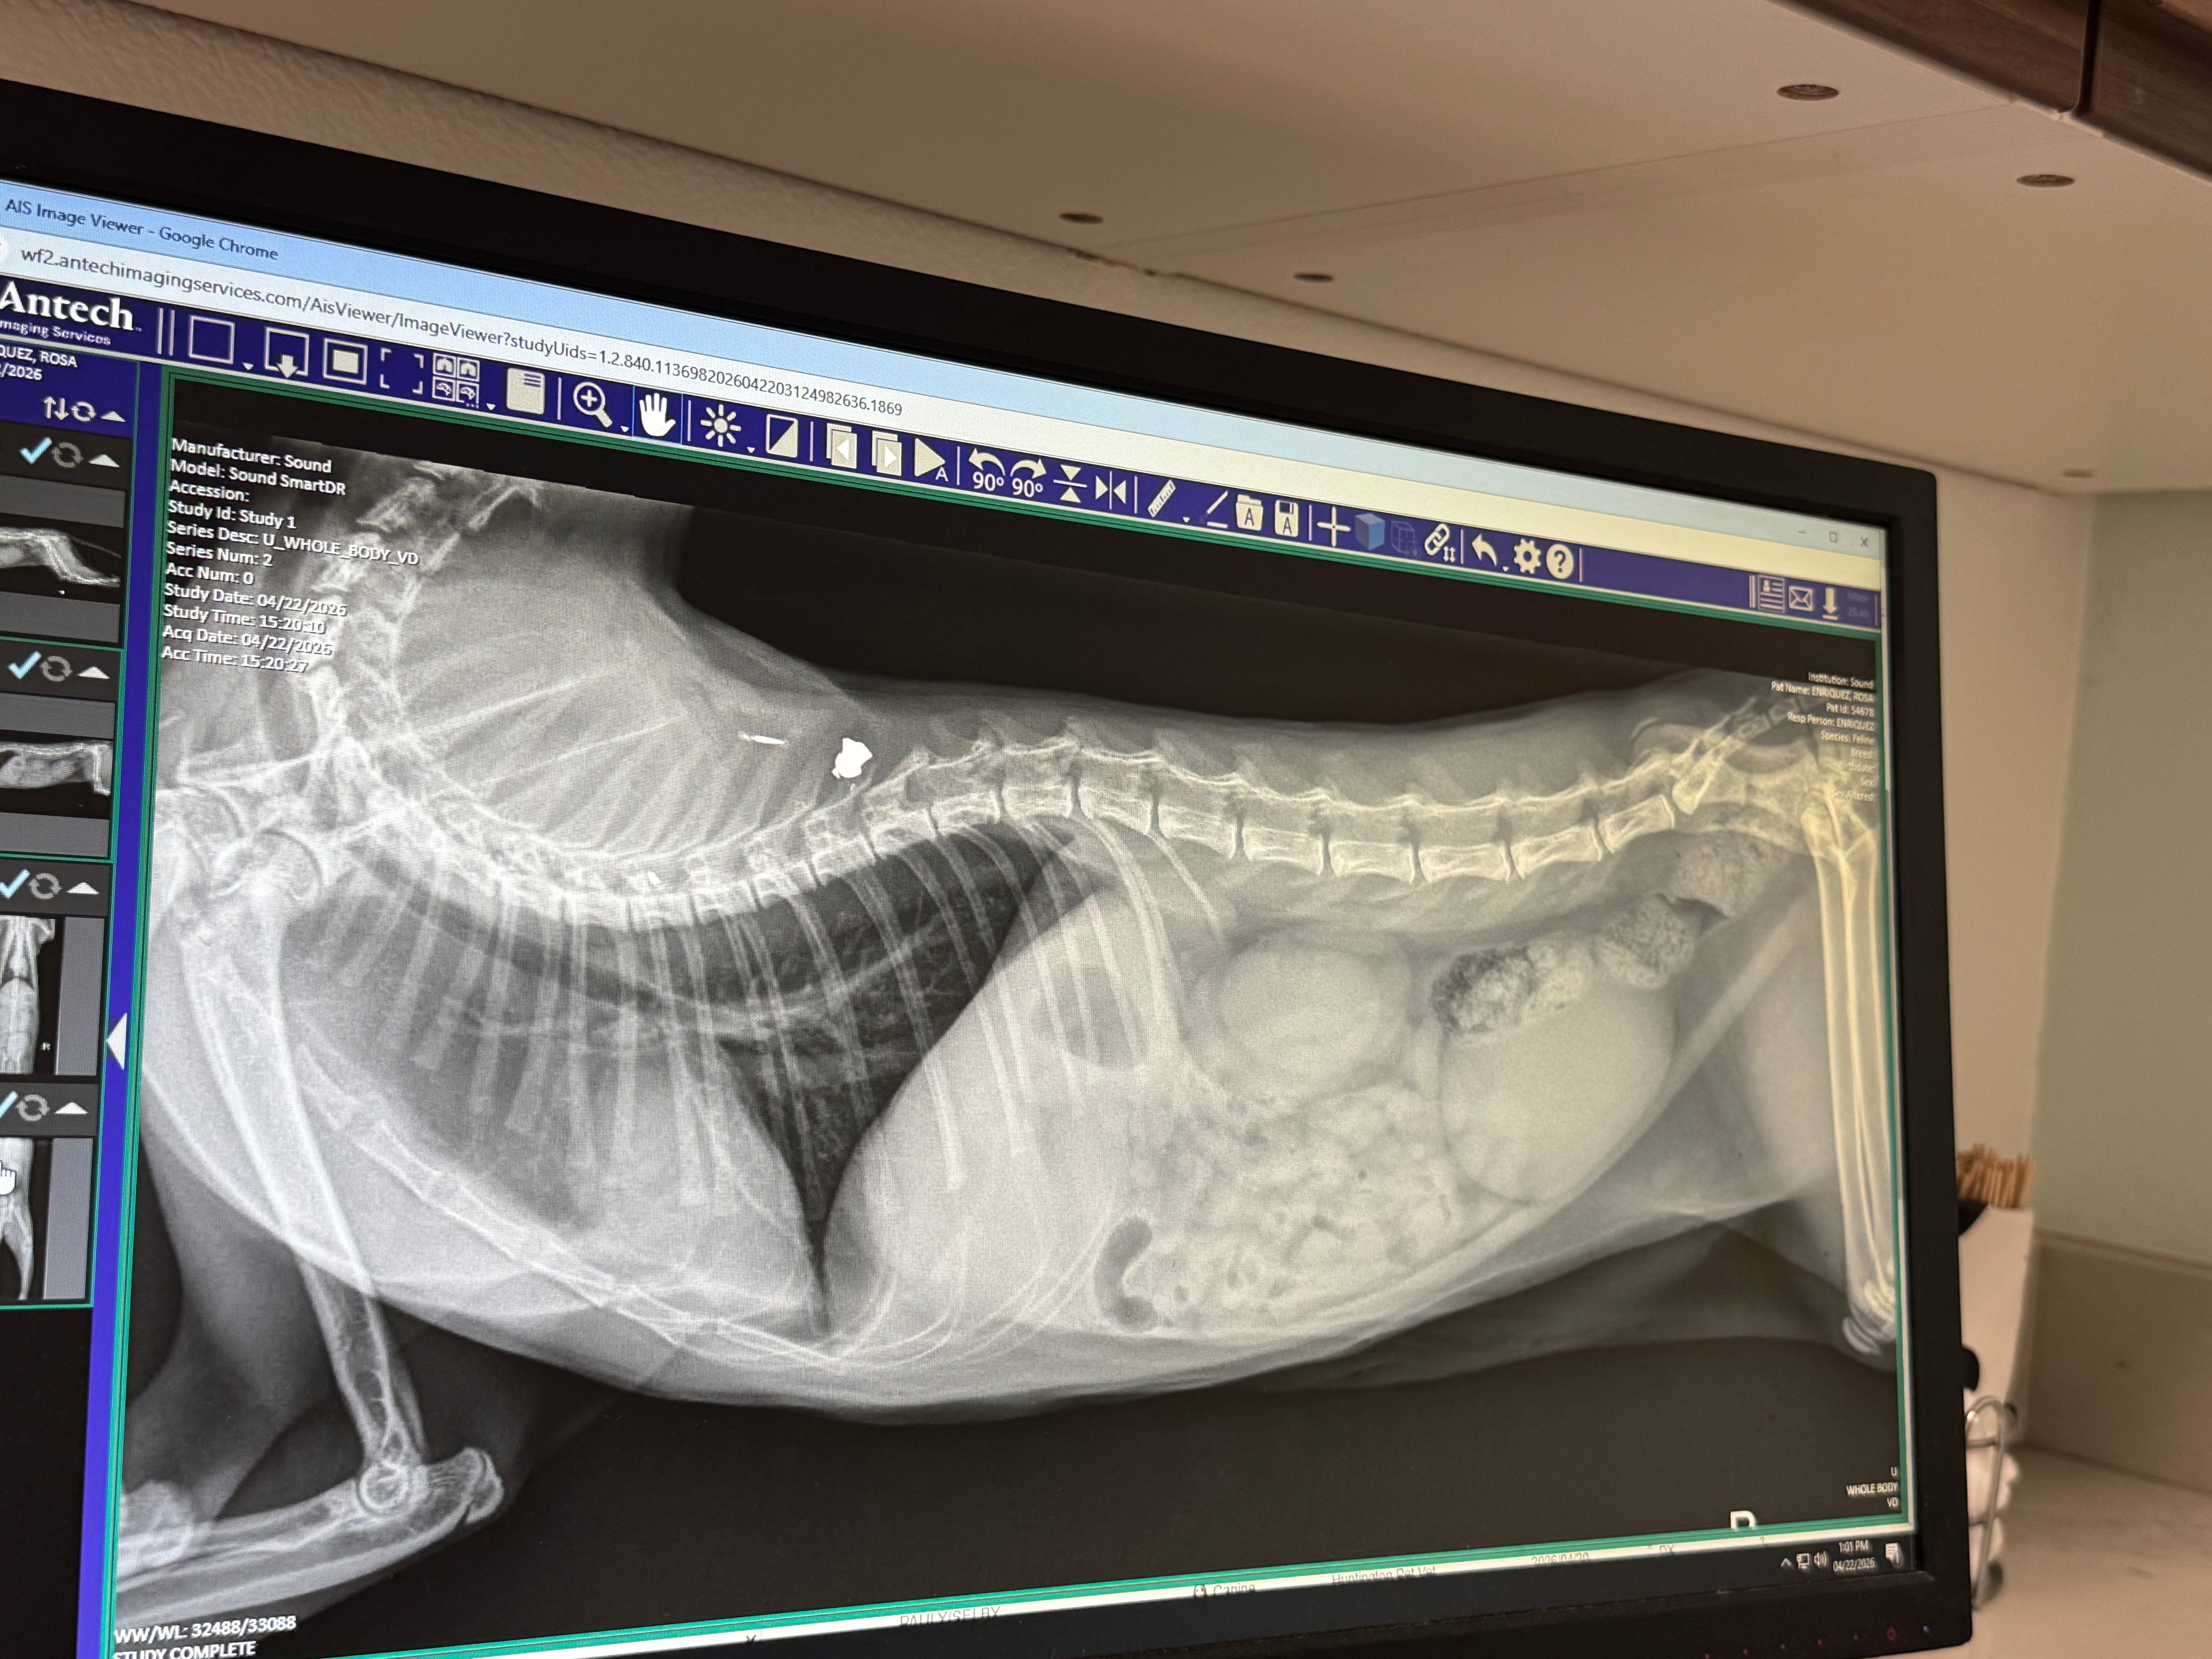

We rushed Jeff to the vet, where he is now being cared for and will need to stay for three days. At first, we thought he might have been hit by a car, but the x-rays revealed something even more heartbreaking—Jeff had been shot. I was able to get approved for CareCredit, but only for a limited amount, and the costs of his care are far beyond what I can cover alone. Jeff will need surgery after observation, depending on his condition, and the emotional toll on my daughter and me has been overwhelming. We can’t understand why someone would do this to such a sweet, loving animal.

The picture attached with a wound is the entrance wound on his shoulder. The x-ray picture shows the bullet right above his spine. As of now he’s not able to walk, but Vet is hoping that’s due to where the bullet is located and states Jeff might be able to walk again but will be limited.